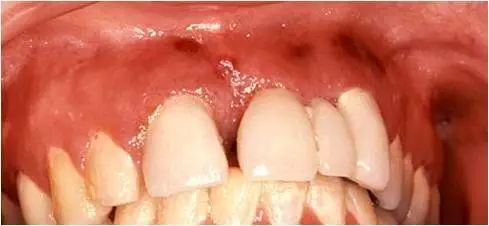

牙龈线形红斑

特征性的表现是沿着牙龈边缘分布的界限清晰的火红色改变,看起来很像 “纹”出来的“牙龈线”,实为牙龈充血。与一般牙龈炎症导致的牙龈充血不同,它的病因并非牙菌斑,患者通常口腔卫生状况良好,很少甚至没有牙菌斑。